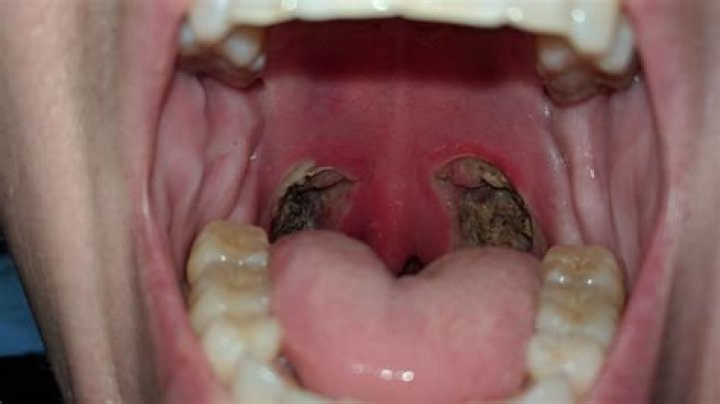

Learn about the causes, treatment, and recovery process of a hole in the throat after a tonsillectomy. Find expert advice and personalized care at Statcare.